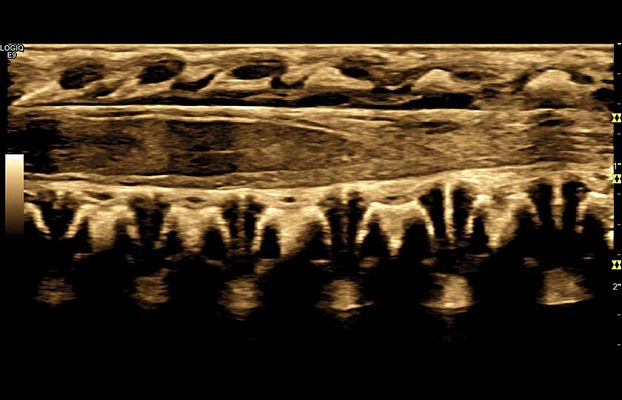

Клинические изображения

- Tissue Velocity Imaging (TVI) - тканевой допплер.

- Stress Echo - опция стресс-эхо.

- Auto EF - опция автоматического недопплеровского измерения глобальной сократительной способности левого желудочка.

- CARDIAC STRAIN - AFI - режим недопплеровской автоматической оценки региональной сократительной функции левого желудочка, степени деформации миокарда.